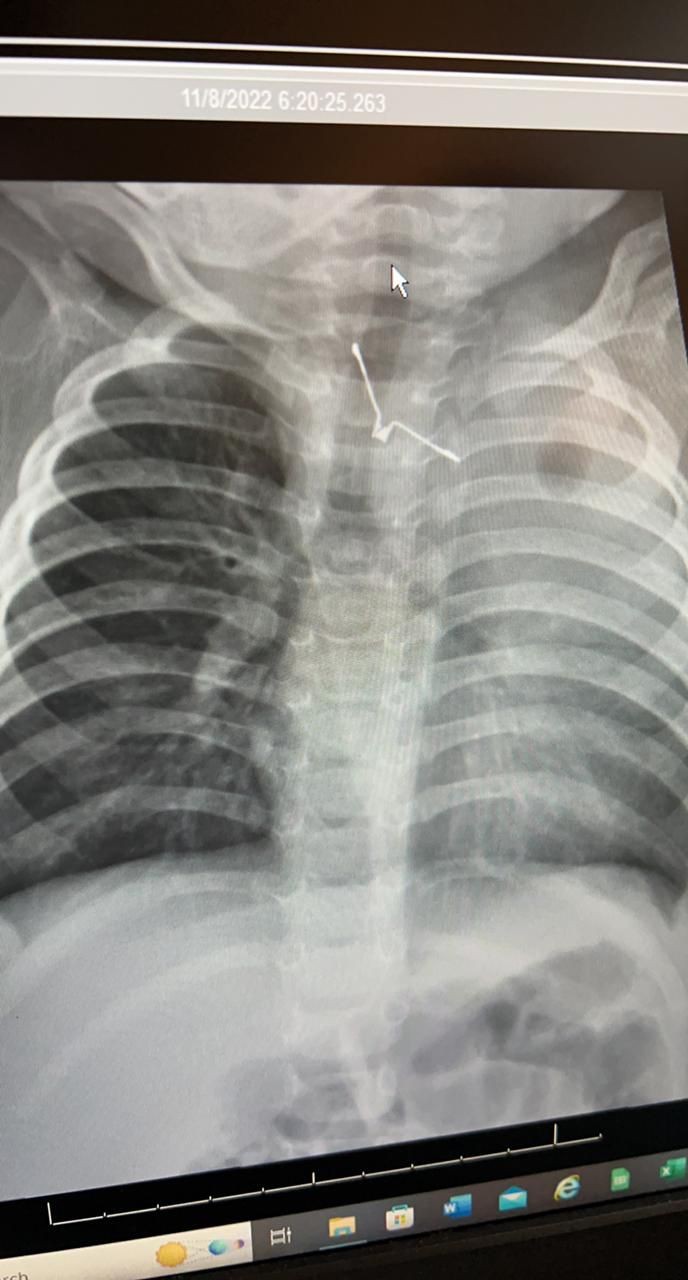

وأوضحت أن الفريق الطبي المشرف على الحالة قام على الفور بعمل التحاليل والإشاعات اللازمة، وتم إدخال الطفلة لغرفة العمليات بشكل عاجل؛ وذلك لاكتشاف جسم معدني حاد الأطراف بلعته الطفلة، وبقي عالقاً في المرئ، مما يسبب لها مضاعفات صحية خطيرة، لو تم تحريكه بأي طريقه خاطئة.

وأفادت الصحة بأن الفريق الطبي نجح في مده زمنية تقارب الـ (4) ساعات من إخراج الجسم الغريب بالمنظار وبحذر شديد؛ حتى لاتصاب الأنسجة المحيطة به بأي جروح، وتتمتع الطفلة حاليًا بصحة جيدة ومازالت تحت العناية لإكمال فترة الشفاء.